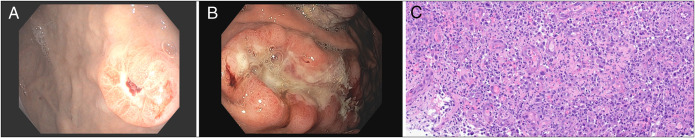

当癌症爆发:识别胃转移灶中的火山灶。

When Cancer Erupts: Recognizing the Volcano Lesion in Gastric Metastases.